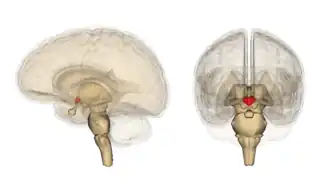

Гипоталамус является частью промежуточного мозга. Он образует основание и стенки нижней части третьего желудочка. Название своё он получил от греч. гипо- (под, внизу) и таламос (чертог, спальня), так как он располагается под таламусом. Гипоталамус отделён от таламуса гипоталамической бороздой (лат. sulcus hypothalamicus). Анатомические границы гипоталамуса определены недостаточно чётко, что связано с тем, что некоторые группы клеток заходят в соседние области, а также с некоторой неопределённостью в терминологии[3]. Считается, что спереди (рострально) гипоталамус ограничен терминальной пластинкой (лат. lamina terminalis), а его задняя (каудальная) граница — воображаемая линия от задней комиссуры (лат. commissura posterior) до каудальной поверхности сосцевидных тел. Дорсолатерально гипоталамус доходит до медиального края мозолистого тела[4].

В нижней части гипоталамуса выделяются такие структуры, как сосцевидные тела (лат. corpus mamillare), серый бугор (лат. tuber cinereum) и воронка (лат. infundibulum). Воронка отходит от серого бугра, средняя часть воронки приподнята и называется срединным возвышением (лат. eminentia mediana), которое в некоторых классификациях относят к серому бугру, а в некоторых — к нейрогипофизу[5]. Срединное возвышение содержит кровеносные сосуды, переносящие выделяемые гипоталамусом вещества в гипофиз. Нижняя часть воронки переходит в ножку гипофиза.